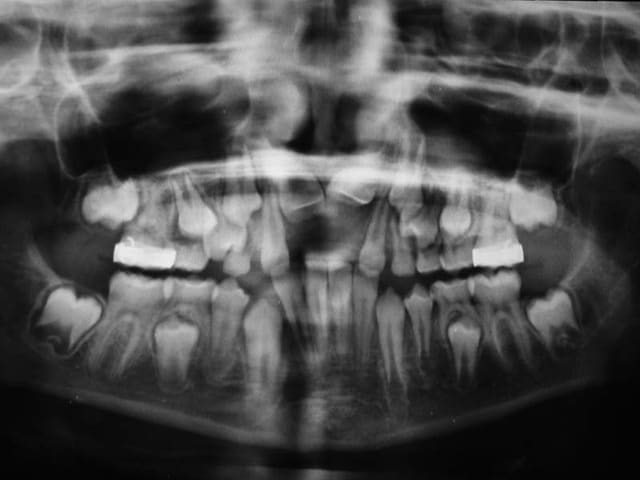

Patient 9 ans

La mère vient consulter car les Inc. centrales sont absentes

bien qu’on lui ait extrait les lactéales, il y a 2 ans

La chirurgie est décidée : ablation des odontomes, ce qui va permettre l’éruption des centrales

Seule la 11 arrive sur l’arcade

Il faut donc faire une 2° chirurgie et coller un anneau de traction

Pourquoi la 11 est elle descendue et pas la 22 ?

sur la Rx. avant Chir., on voit que la 22 est en position plus apicale que la 21

voici une Rx. après Chir., ou on voit que le dégagement osseux de la 22 est moins important que sur la 21, sans doute à cause de sa position plus apicale

ce qui expliquerait pourquoi la 22 est restée bloquée